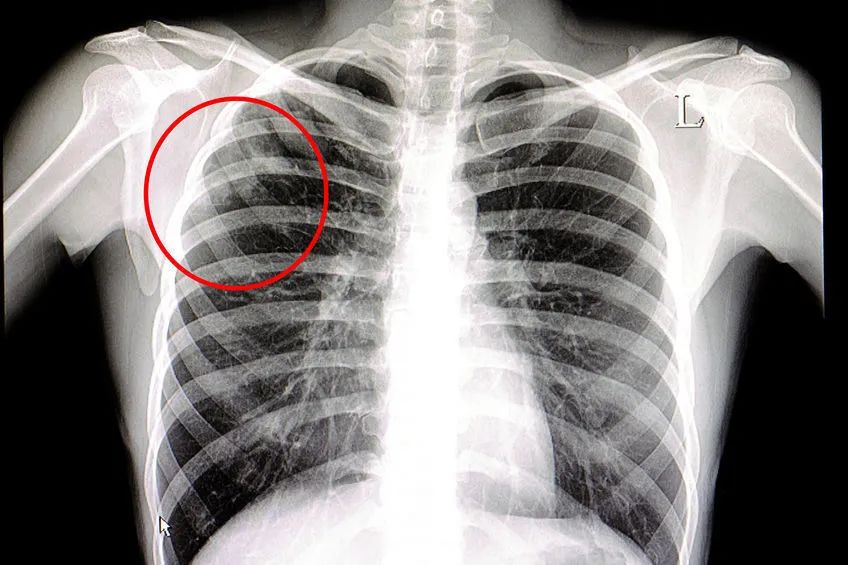

肺结核的影像学表现及鉴别诊断

肺结核x线图

肺结核的影像学表现及鉴别诊断

肺结核的影像学表现及鉴别诊断

肺结核的影像学表现及鉴别诊断

肺结核的影像学表现及鉴别诊断

肺结核的分型及影像学表现

肺结核的影像学表现及鉴别诊断